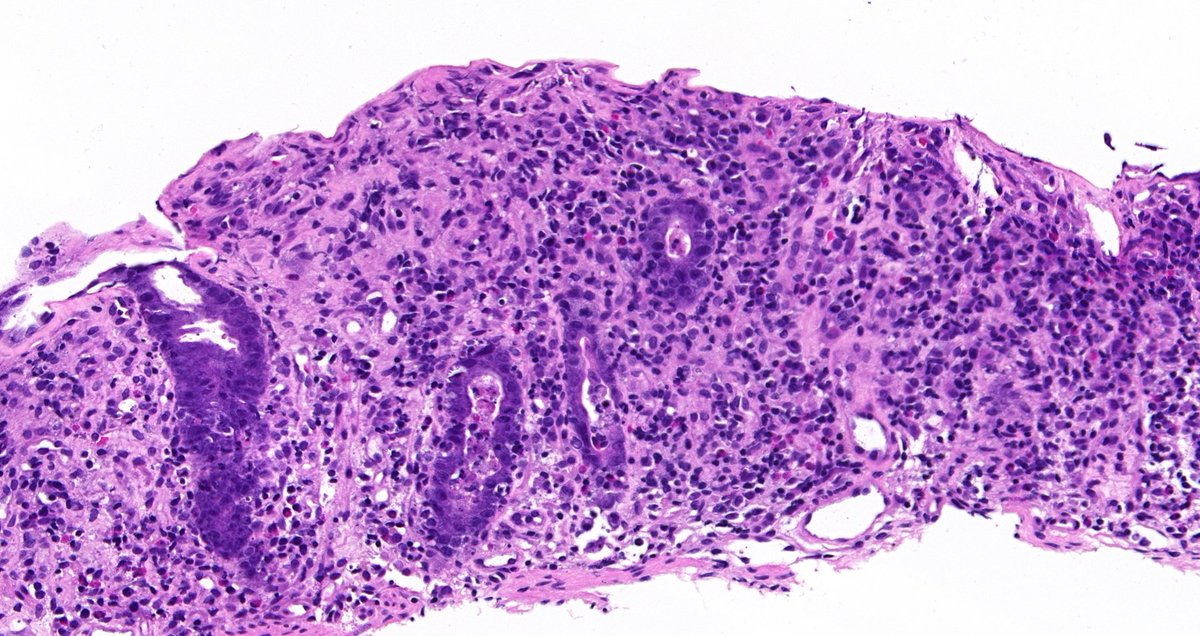

💜 is full with #PurplePride. @NU_Pathology residents @AlcinoGama & @FeliPathMD were recognized for their innovative work in #SurgicalPathology training at @NUFeinbergMed Education Day! @NU_FAME @McGawGME @DanielJBrat @NayarRitu @novo_pathology @bonnie_choy